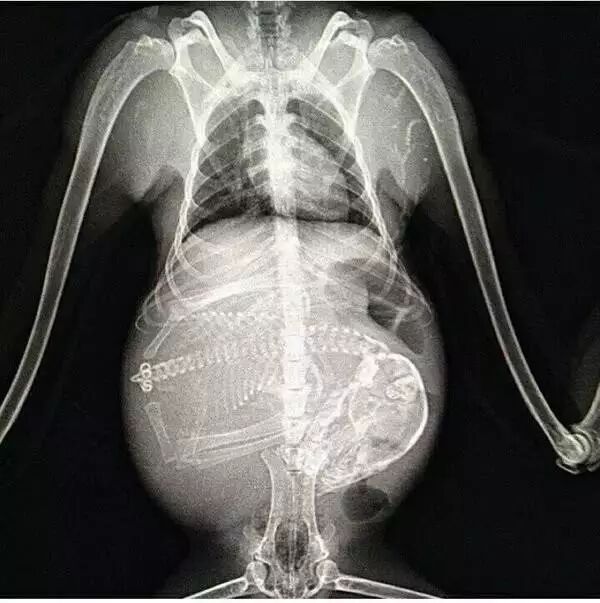

NO.3

<怀孕的猫咪>

猫咪肚子装得好乱,

强迫症好想帮它整理一下!